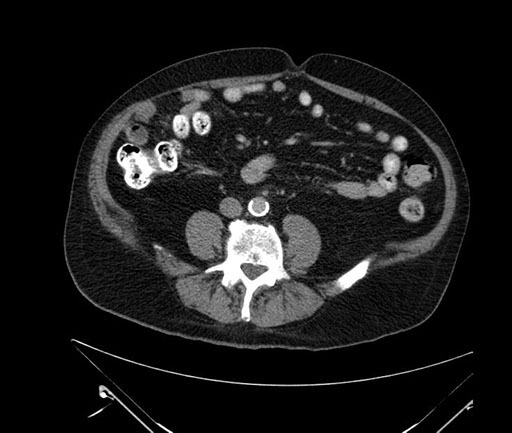

Imaging Analysis

Look through the patient's CT scan to identify any areas of concern for the necessary procedure.

Based on your CT findings, which issue(s) would give reason for "planned slowing down moment(s)" in this case?